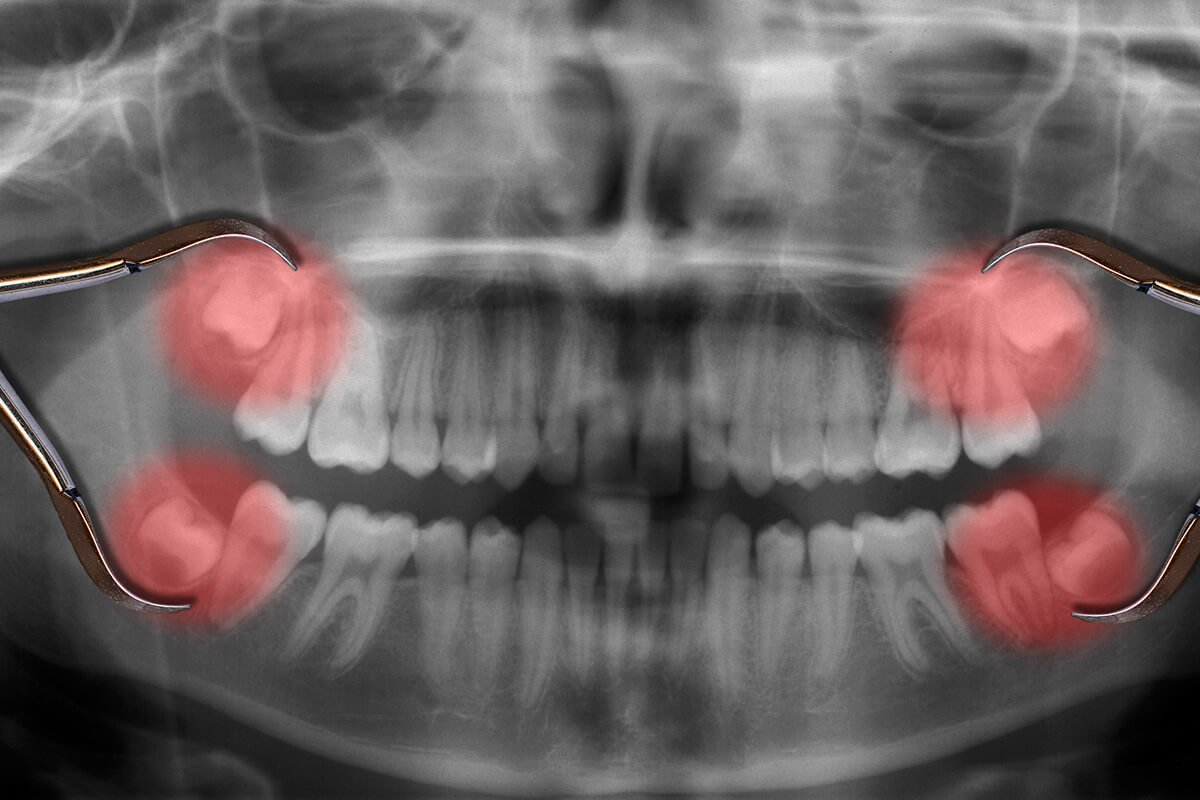

Wisdom teeth removal is a common surgical procedure to extract the third molars, which usually emerge between the ages of 17 and 25. Many people experience pain, swelling, or infection due to impacted wisdom teeth, where the tooth doesn’t fully erupt. Overcrowding and misalignment of teeth can also result. The procedure typically involves local anaesthesia, and recovery includes managing swelling and discomfort. Post-surgery care includes rest, soft foods, and avoiding smoking. While not always necessary, removing wisdom teeth can prevent future complications, such as infections, gum disease, and damage to neighbouring teeth. Wisdom Teeth Removal:

• Prevents Crowding: Wisdom teeth can push against other teeth, leading to misalignment or overcrowding. Removing them creates space, allowing teeth to remain properly aligned.

• Reduces Infection Risk: Impacted or partially erupted wisdom teeth are prone to gum infections and decay. Extraction helps prevent painful infections like pericoronitis.

• Avoids Cysts and Tumors: Cysts or tumors can form around impacted wisdom teeth, damaging the jawbone and neighboring teeth. Early removal reduces this risk.

• Improves Oral Hygiene: Wisdom teeth in hard-to-reach areas make cleaning difficult, leading to decay. Removal enhances oral hygiene and reduces cavities.

• Prevents Jaw Damage: Impacted wisdom teeth can damage the jaw and surrounding nerves. Removing them minimizes the risk of long-term bone and nerve damage.